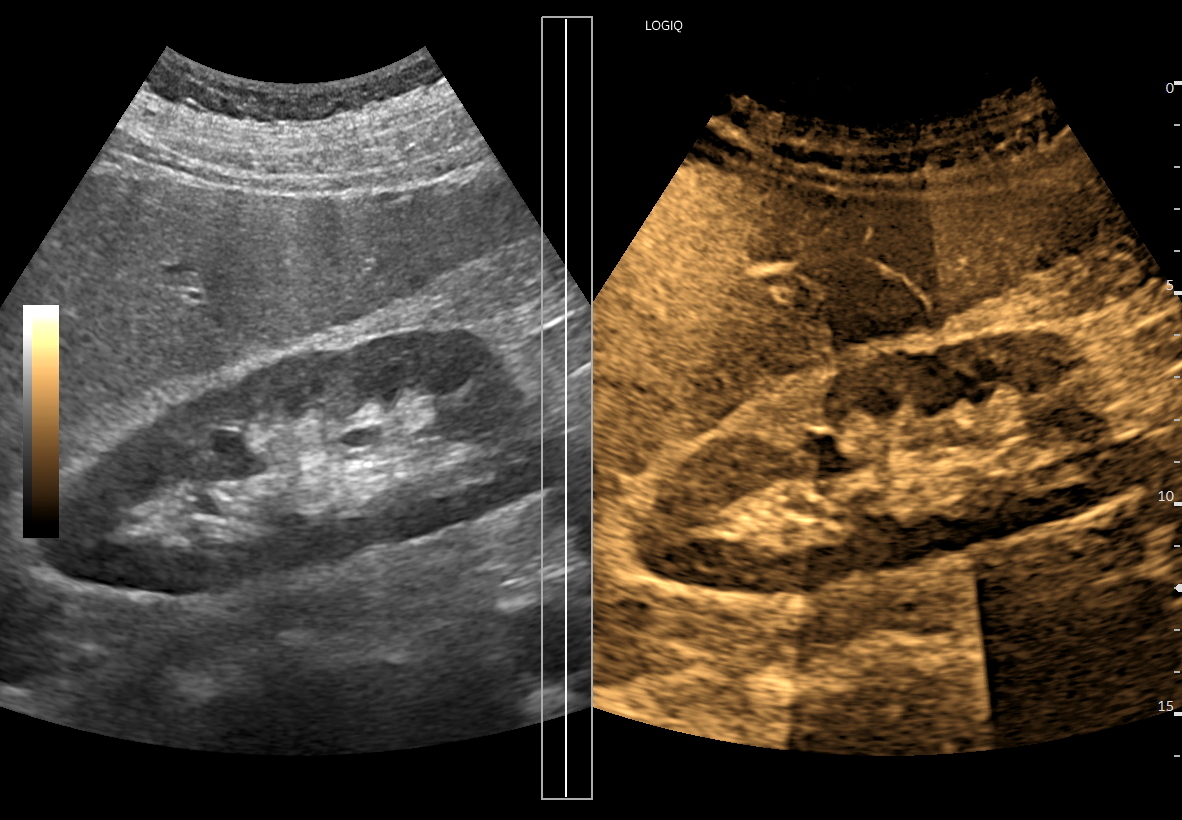

Oprócz zastosowań stricte naczyniowych tryb B-flow znajduje zastosowanie przy poprawie obrazowania struktury narządów wewnętrznych i ich zarysów. Otóż wykorzystując zasady powstawania obrazu w tym trybie, tj. generowanie silnego sygnału, który odpowiada poruszającemu się elementowi, przy implementacji delikatnych acz zdecydowanych ruchów głowicą USG, w ruch można wprawić cały narząd lub grupę sąsiadujących struktur, przez co możliwe staje się stworzenie obrazów struktur miąższowych oraz całych narządów. Jednocześnie stosując odpowiednio intensywny ruch litych struktur tkankowych można niejako oszukać software, tj. oprogramowanie aparatu dokonuje supresji sygnału poruszającej się krwi, przez co uzyskuje się obraz danego narządu o znacznie większej kontrastowości i szczegółowości aniżeli w podstawowym obrazowaniu w skali szarości (w trybie B).